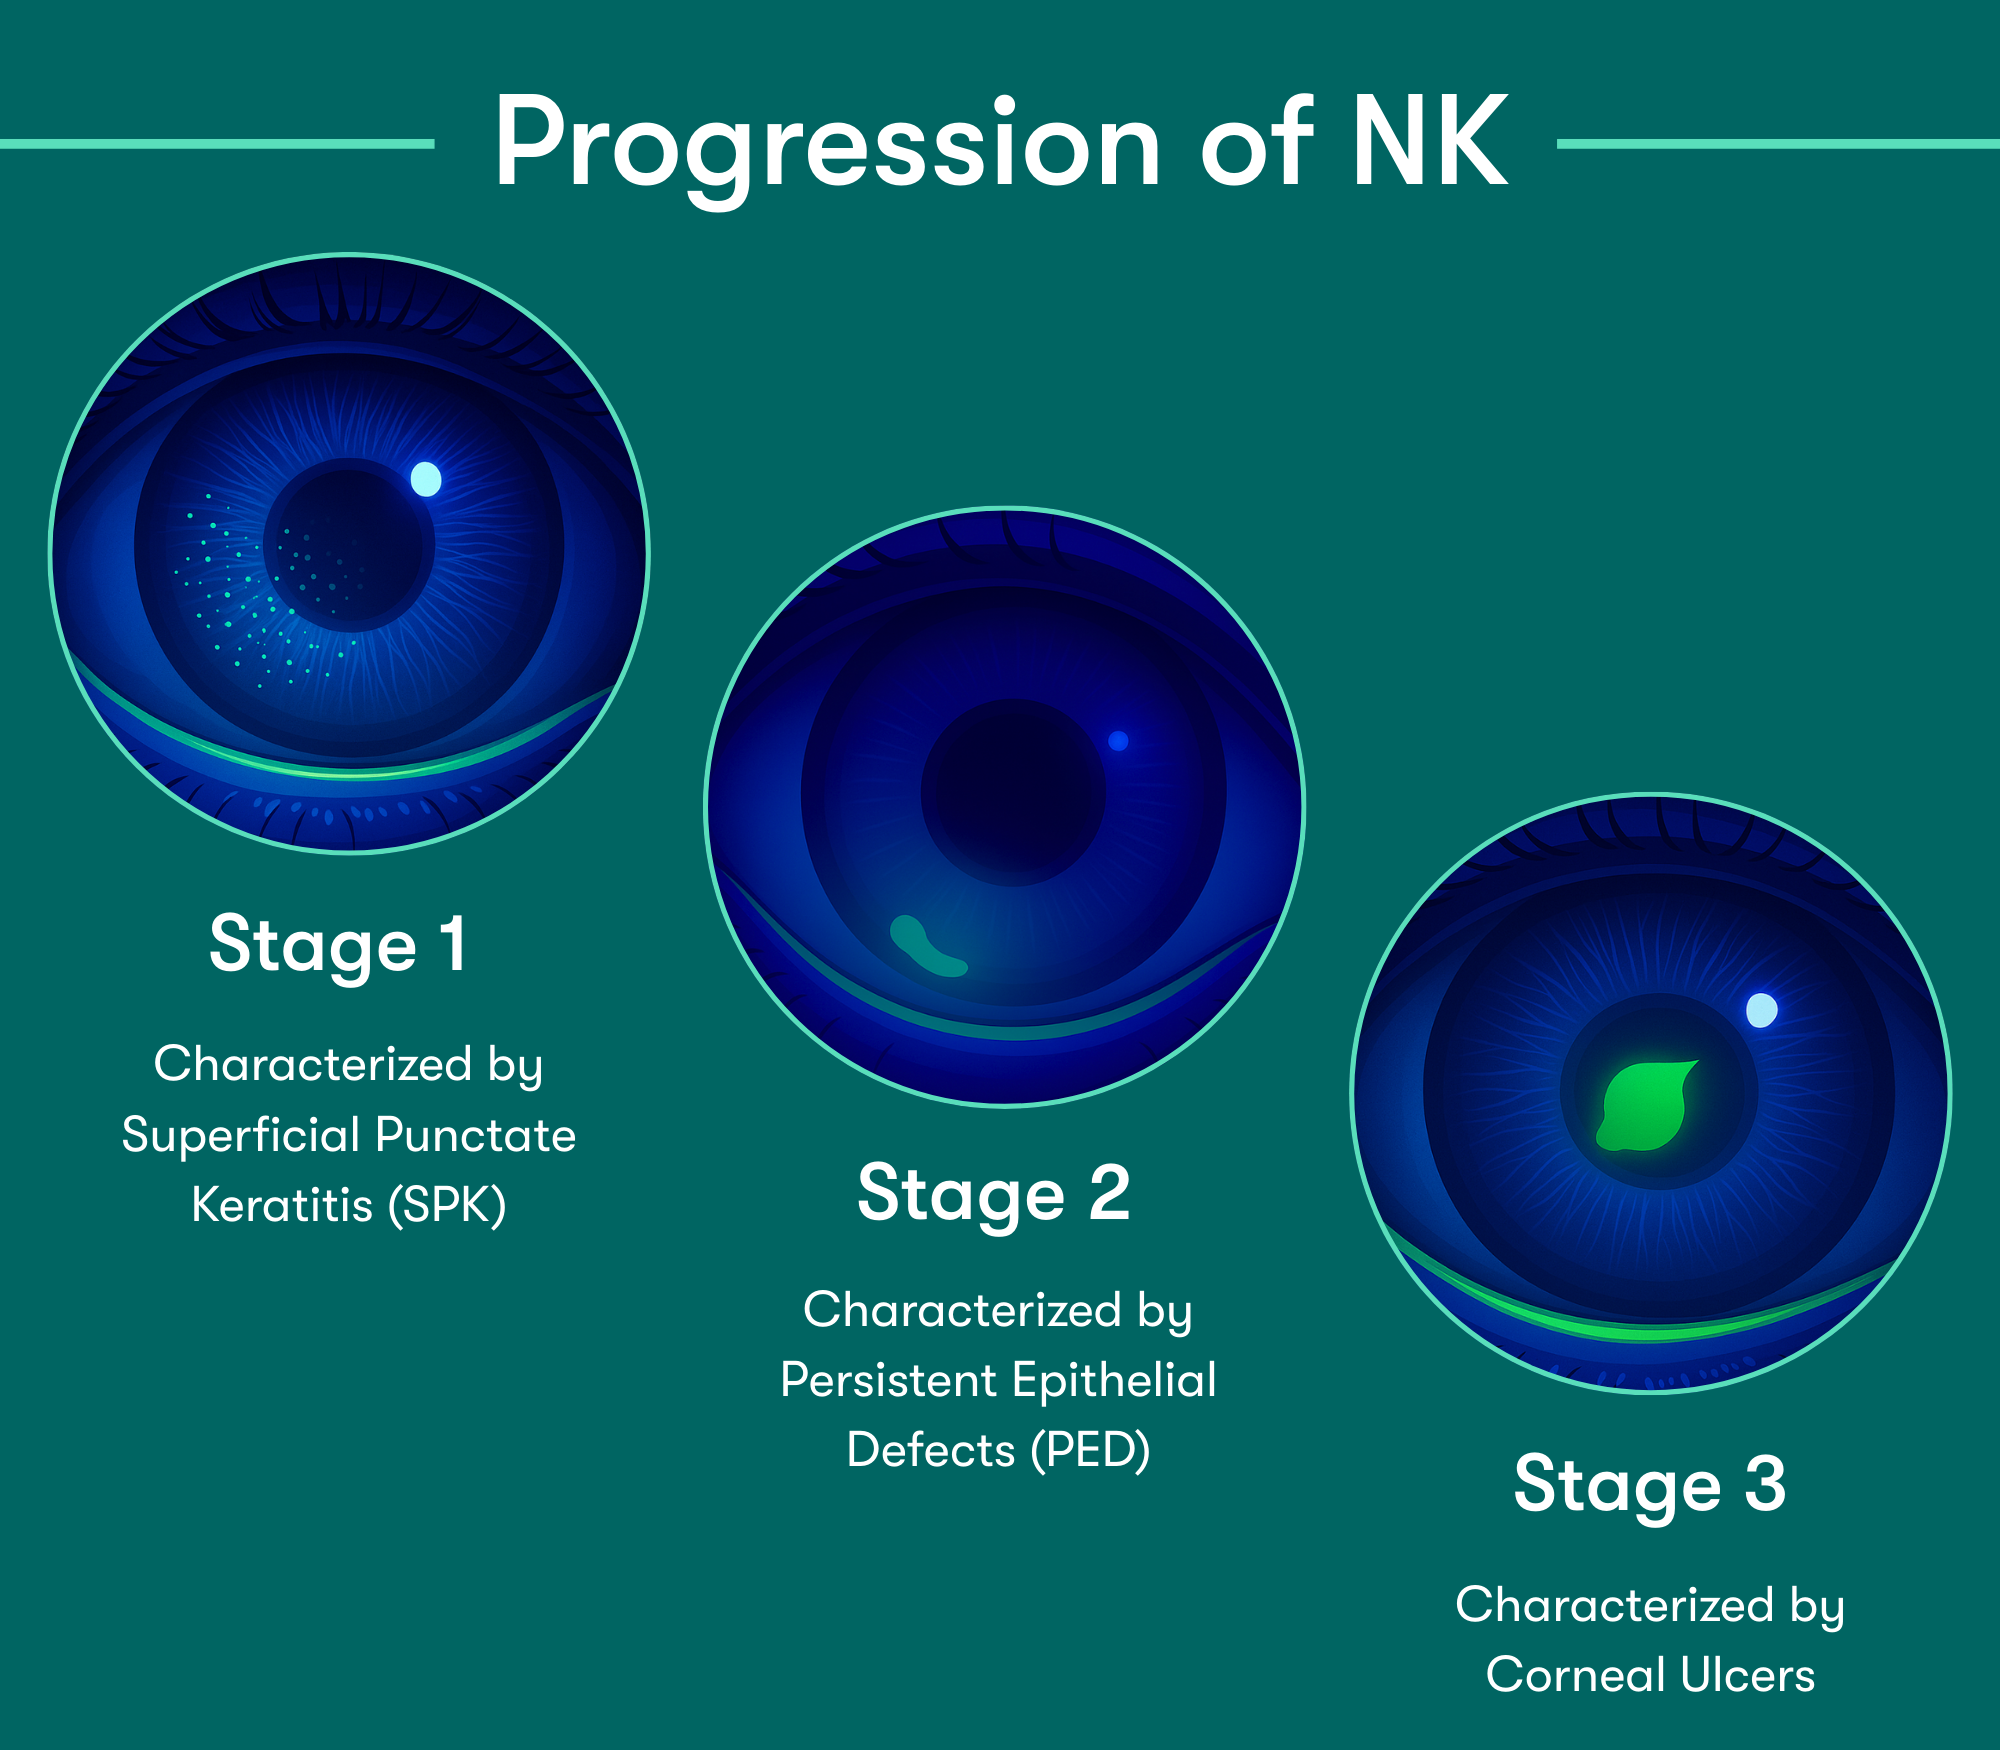

Understanding NK and the Power of Early Intervention:

NK is a corneal degenerative disease characterized by a reduction of corneal sensitivity.2 In NK, corneal innervation by the trigeminal nerve is impaired.2

According to the Mackie classification, Stage 1 NK begins as early as Punctate Epithelial Keratitis (PEK).3 Lack of early detection can lead to corneal epithelial breakdown, impairment of healing, and development of corneal ulceration, melting, and perforation.4